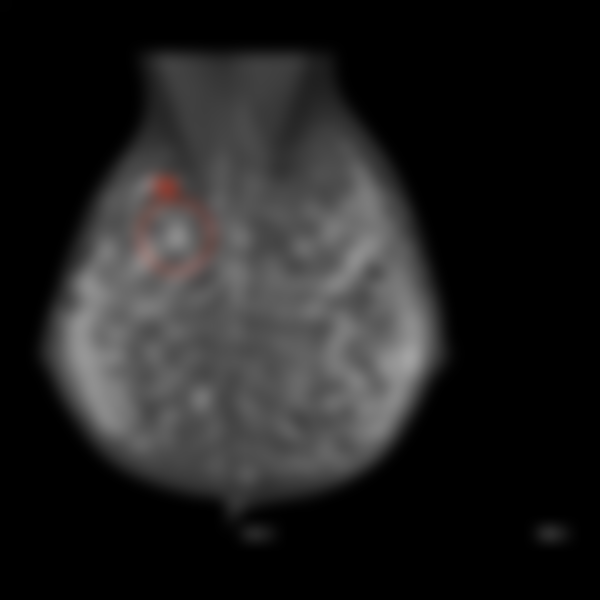

80.下列何者可提供醫師於診斷上的第二意見(second opinion)?

(B)CAD(computer-aided diagnosis)